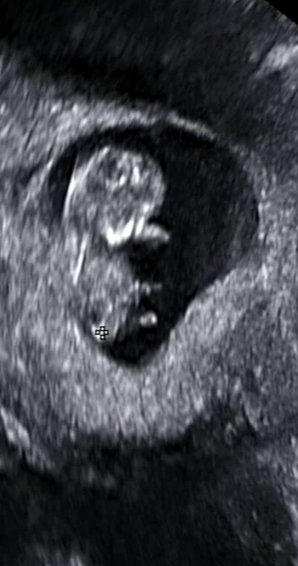

처음 임신을 알게된건 임신 극초기때였습니다. 계속 기다리던 아기라 계속 테스트기를 하기도 했고 느낌이 이상해 산부인과를 방문했지만 초음파로는 보이지 않았고 피검사로 임신을 했다는 사실을 알게됐습니다. 5주가 됐을무렵 아기집이 생기고 난황이 보였습니다.

점점 커갈때마다 임산부는 힘들어하고 아기도 걱정되고 심하게 배가 땡기고 아플때마다 병원을 방문했습니다. 조금씩 출혈이 초음파에서 잡히기도 했고 의사선생님께서는 계속 눕거나 안정을 취해야 한다고만 하셨습니다. 토를 안하려고 신맛이 나는 사탕,젤리를 자주 먹었지만 갑자기 나오는 토는 참을수가 없습니다. 밖에 나갈때는 비닐이 필수였습니다.